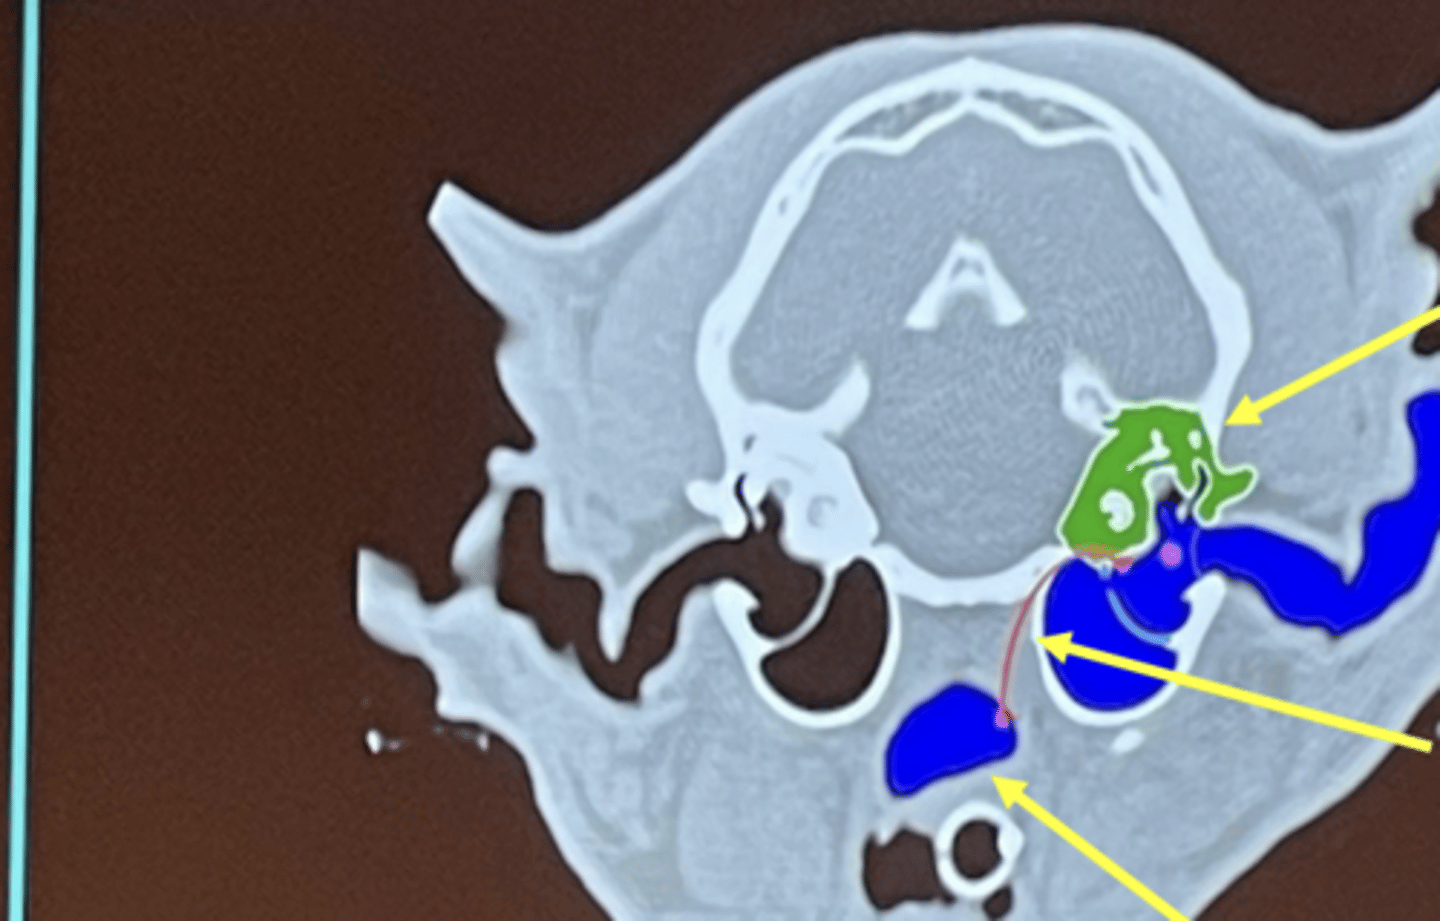

What is the top arrow pointing to (green)?

inner ear

What is the middle arrow pointing to?

eustachian tube

What is the bottom arrow pointing to?

nasopharynx